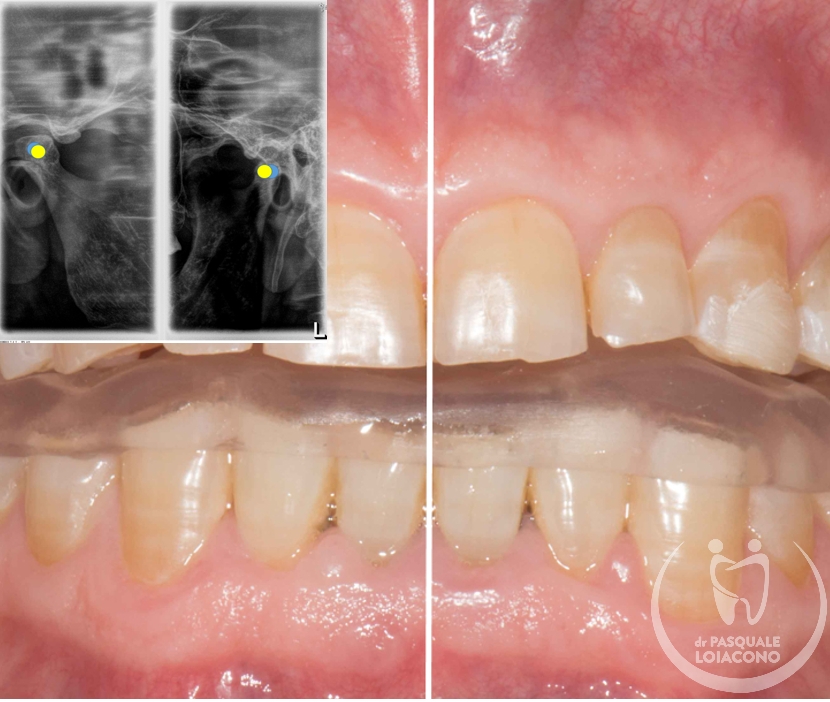

In generale nel funzionamento della bocca è preferibile che ci sia la simmetria tra le parti destra e sinistra, perché segno di equilibrio muscolare. Le asimmetrie delle arcate sono spesso la conseguenza di abitudini di masticazione prevalente su un solo lato, condizione non ottimale perché potrebbe creare tensioni nel nostro sistema posturale e sulle articolazioni della mandibola.

E’ importante notare come sia la chiusura dentale a influenzare la posizione nello spazio dell’articolazione. Per questo in caso di problemi articolari è necessario costruire un bite di “riposizionamento mandibolare”, cioè un apparecchio costruito per mantenere attraverso i denti la mandibola e le sue articolazioni in una posizione corretta.

Quando ci sono problemi articolari della mandibola è necessario ricercare un’occlusione dentaria che rimetta il sistema il più possibile in equilibrio. L’organo della masticazione non è costituito solo da denti, ma anche da articolazioni e componenti neuromuscolari, e solo quando tuti i componenti sono in armonia tra loro si può avere salute e benessere. In realtà non tutti gli studiosi sono d’accordo su questioni fondamentali e non esiste visione unanime. Questo vuol dire che potreste incontrare un odontoiatra che sconsiglia qualsiasi trattamento, se non fisioterapia e massaggi o addirittura solo terapia psicologica di sostegno. All’opposto esistono scuole di pensiero che identificano nell’occlusione il fattore scatenante di una patologia che comunque resta complessa e multifattoriale. Da dentista desidero che la bocca funzioni bene e segua le regole stabilite, perché considero comunque positiva questa condizione, e quindi cerco di riportare l’occlusione del paziente verso una condizione il più possibile ideale.